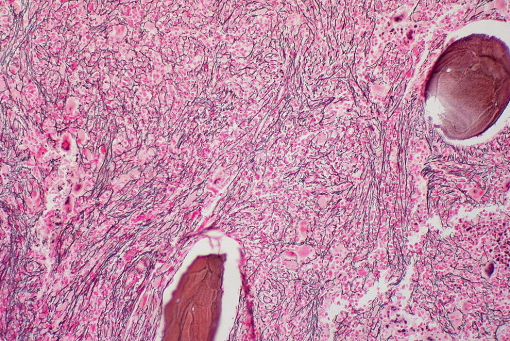

● развитие экстрамедуллярного кроветворения и миелофиброза (в разной степени);

Дифференциация важна для терапии. Однако она затруднена на ранних стадиях болезни, и четкое назначение часто невозможно. При всех заболеваниях может затруднить дифференциальную диагностику стойкий тромбоцитоз. При сборе анамнеза следует обратить внимание на наличие вышеуказанных симптомов. В костном мозге может произойти экстрамедуллярное кроветворение. Это может проявляться как спленомегалия и/или гепатомегалия при физикальном осмотре. С помощью гематологических, молекулярно-генетических, цитологических и гистологических исследований можно добиться правильной классификации. Диагностика ХМПЗ включает: